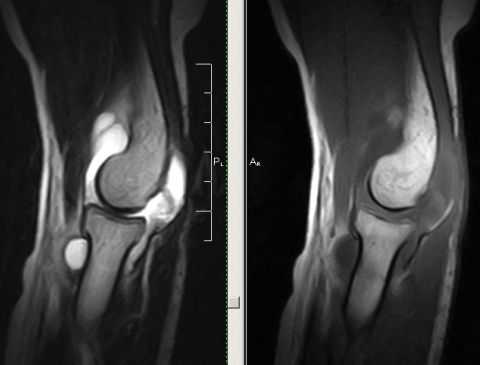

(Слева) На боковой рентгенограмме определяется задний вывих предплечья, в том числе локтевого отростка и головки лучевой кости. Большой отломок головки лучевой кости расположен кпереди от головки мыщелка плечевой кости.

(Справа) На передне-задней рентгенограмме определяется латеральное направление типичного вывиха. Видна вывихнутая головка лучевой кости с большим дефектом, вывихнутая локтевая костью и отломок перелома головки лучевой кости. Примерно 90% вывихов предплечья являются заднебоковыми по направлению. (Слева) На боковой рентгенограмме у подростка 11 лет определяется задний вывих локтевого и лучеголовчатого суставов. Отломки находятся в суставе.

(Справа) На передне-задней рентгенограмме у этого же пациента можно видеть медиальное смещение лучевой и локтевой костей. Примерно 90% вывихов локтевого сустава являются заднебоковыми. Видимые в боковой проекции отломки исходят из головки мыщелка плечевой кости и головки лучевой кости. (Слева) В передне-задней проекции локтевого сустава после попытки закрытого вправления заднебокового вывиха предплечья видны отломки головки лучевой кости и венечного отростка.

(Справа) На боковой проекции у этого же пациента определяется задний вывих лучеголовчатого сустава с множеством костным отломков в суставе и дефект в головке лучевой кости. Локтевой сустав неконгруэнтный, что указывает на неполное вправление.